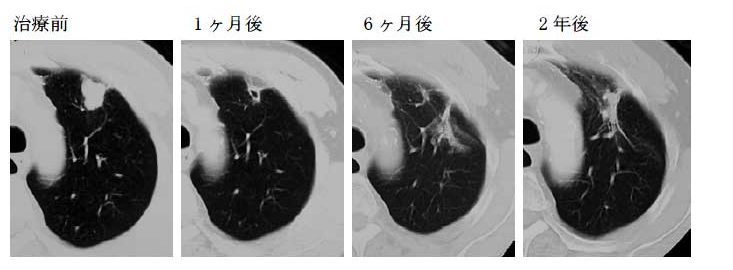

肺癌是位于世界發(fā)病率二位,死亡率一位的惡性腫瘤,質(zhì)子可以治療I期(僅質(zhì)子治療)或II-III期(質(zhì)子束聯(lián)合化療)、呼吸功能良好,無(wú)間質(zhì)性肺炎的肺癌患者。根據(jù)日本國(guó)立癌癥研究中心東醫(yī)院的數(shù)據(jù),早期非小細(xì)胞肺癌經(jīng)質(zhì)子治療后,2年局部無(wú)復(fù)發(fā)生存率為80%,總生存率為84%;將早期非小細(xì)胞肺癌大小按照3cm為分界線分布,在3cm以下的肺癌患者經(jīng)質(zhì)子治療后2年局部無(wú)復(fù)發(fā)生存率為94%,3cm以上的肺癌患者2年局部無(wú)復(fù)發(fā)生存率為62%。另外,根據(jù)相關(guān)臨床數(shù)據(jù)指出,進(jìn)行性肺癌(主要為Ⅲ期)在質(zhì)子治療與化療聯(lián)合治療后,1-5年的生存率分別為92%,75%,71%,56%,56%。因此對(duì)于肺癌患者而言,質(zhì)子治療是一個(gè)不錯(cuò)的選擇。

經(jīng)質(zhì)子治療2年后,肺部腫瘤消失|圖源:日本國(guó)立癌癥研究中心東醫(yī)院官網(wǎng)